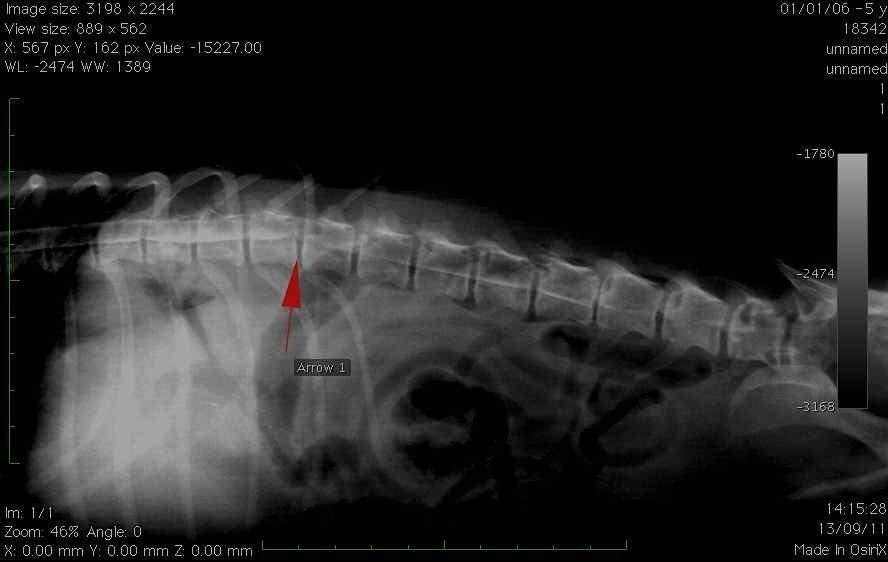

Unsere chirurgische Abteilung führt auch Wirbelsäulenoperationen durch:

- Die Operationen von Bandscheibenvorfall die die ersten Pathologien geworden sind, denen man begegnet ist Neurologie im Hund.